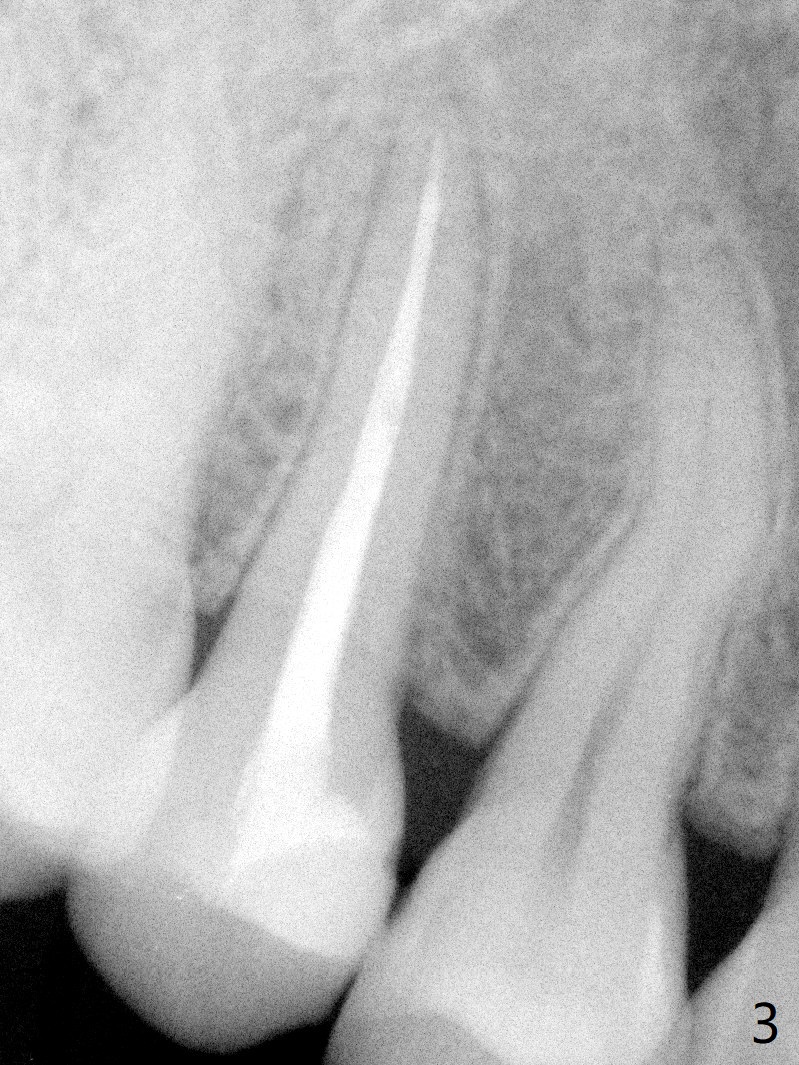

A 29-year-old woman presented to office with multiple amalgam restoration 7 years ago. The tooth #4 developed acute pulpitis 7 months later (Fig.2). The tooth has 2 fused canals; after RCT, composite was placed; after discussion, the patient chose no crown (Fig.3). There is no recurrent periapical radiolucency or tooth fracture 2.5 (Fig.4) or 6.5 (Fig.5,6) years postop.